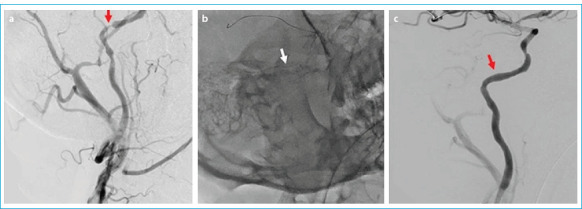

目的:评价有症状的颅内狭窄患者对药物干预反应不充分的血管内治疗的疗效和临床结果。方法:该研究纳入了32例于2021年12月至2023年12月期间因颅内高级别(70%-99%严重程度)动脉粥样硬化性狭窄接受血管内治疗的患者。患者在最近三周内未发生任何急性缺血性或出血性梗死,基线时改良兰金量表评分≤3分,尽管接受了最好的药物治疗,但仍发生过短暂性缺血性发作或非致残性卒中。记录技术和临床成功率、死亡率和并发症发生率。结果:纳入研究的32例患者中,男性占62.5% (n=20),平均年龄66.4±10.09岁。43.8% (n=14)的患者行颅内颈内动脉支架植入术,37.5% (n=12)的患者行硬膜内椎动脉支架植入术,12.5% (n=4)的患者行大脑中动脉支架植入术,6.3% (n=2)的患者行基底动脉支架植入术。技术成功率100%,临床成功率87.5%。术前平均狭窄度为91.7±6.3%,术后残余狭窄度为22.1±4.7%。Neuroform Atlas®支架系统18例(56.3%),Credo®支架8例(25%),冠状动脉球囊可扩张支架4例(12.5%),LVIS®支架系统2例(6.3%)。28例(87.5%)患者在前30天没有任何症状,2例(6.2%)患者发生缺血性卒中,1例(3.1%)患者发生出血性卒中,1例(3.1%)患者死亡。结论:在精心挑选的患者中进行血管内治疗,量身定制的治疗亚型选择,以及一个经验丰富的多学科团队在手术前、手术中和手术后对患者进行监督,有可能为有症状的颅内动脉粥样硬化性狭窄患者提供安全有效的治疗。

Results: Of the 32 patients included in the study, 62.5% (n=20) were male, and the mean age was 66.4±10.09 years. Stenting was performed on the intracranial internal carotid artery in 43.8% (n=14) of the patients, the intradural vertebral artery in 37.5% (n=12), the middle cerebral artery in 12.5% (n=4), and the basilar artery in 6.3% (n=2). The technical success rate was 100%, and the clinical success rate was 87.5%. The mean degree of stenosis before the procedure was 91.7±6.3%, and the degree of residual stenosis after the procedure was 22.1±4.7%. The Neuroform Atlas® stent system was used in 18 cases (56.3%), Credo® stents in eight (25%), coronary balloon-expandable stents in four (12.5%), and the LVIS® stent system in two (6.3%). Twenty-eight (87.5%) patients did not have any symptoms in the first 30 days, while two (6.2%) patients had an ischemic stroke, one (3.1%) patient had a hemorrhagic stroke, and one (3.1%) died.